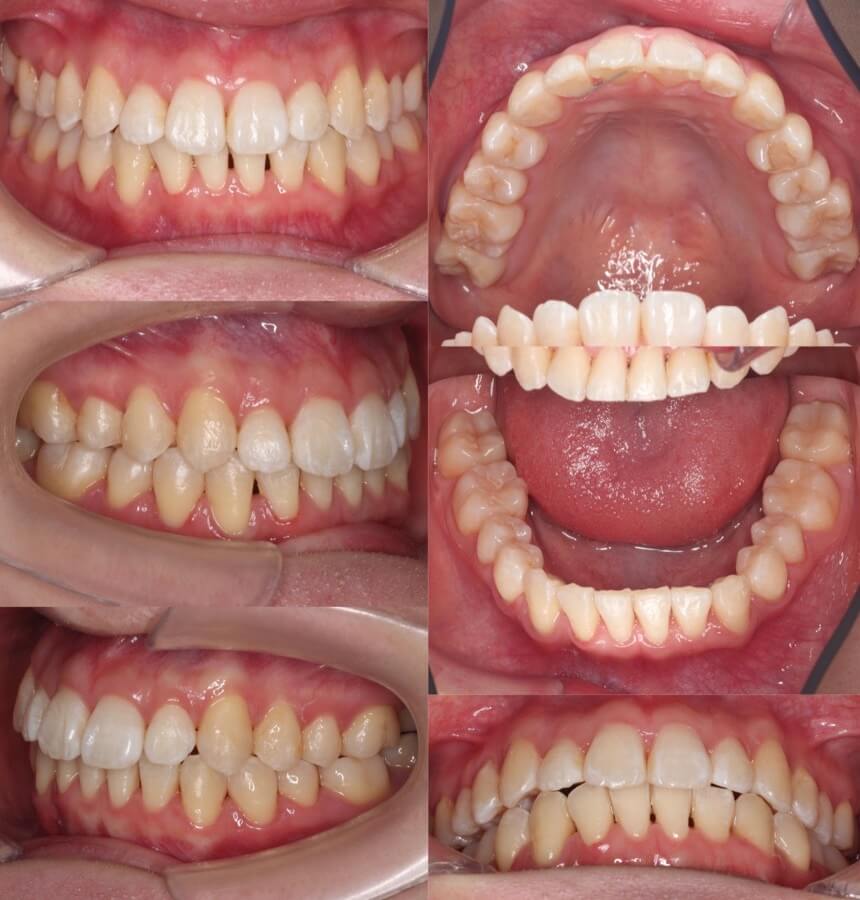

20代女性・軽度叢生・マウスピース型装置

下顎の非対称がある中で、正中線を合わせながらねじれている前歯を整えました。顎間ゴムをしっかりと使用したことが成功の鍵です。

<症例概要> 難易度★★★☆☆

主訴:前歯の突出

年齢・性別:20代女性

住まい:千葉県印西市

症状:叢生・正中線の不一致

治療方針:右下後方移動・左上後方移動・拡大・ストリッピング

治療装置:マウスピース型矯正装置(アライナー装置)

治療期間:1年11か月

アライナー枚数:40+32ステージ

リテーナー:上下フィックスタイプ+クリアタイプ

治療費用:990,000(税込)

代表的副作用:痛み・治療後の後戻り・歯根吸収・歯髄壊死・歯肉退縮

右下と左上と対角の歯並びを後方移動させながら拡大し、前歯を後方移動させながら正中線を一致させました。